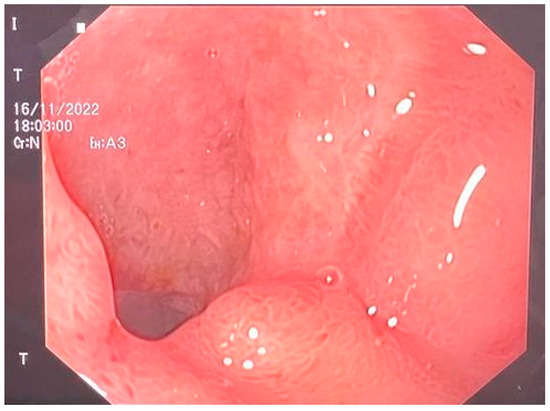

Surgical intervention was decided as the therapy. Upon exploratory laparotomy, we revealed the presence of an advanced adhesion process with a mass formation. This mass was found to be compressing the duodenum and pancreas but was not obstructing the GI tract. Once viscerolysis was performed, the presence of a subphrenic abscess located bilaterally containing purulent, aero-digestive content was confirmed. The evacuation of the abscess was performed via the application of three rubber drainage tubes. Because of the important inflammatory status and the high grade of adhesions, the perforation could not be objectified. An endoscopic evaluation was performed, and we found a duodenal defect in segment I, which was communicating with the residual cavity of the abscess (Figure 1).

Figure 1.

Endoscopic view of the duodenal ulcer.